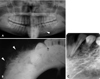

A routine radiographic examination was performed. The resulting panoramic radiograph revealed a well-defined multilocular radiolucency extending from the left mandibular canine to the left mandibular second premolar with the presence of small loculations and fine trabeculae (Fig. 2A). The roots of the left mandibular premolars were displaced laterally and showed no resorption. The mandibular occlusal radiograph showed bone spicules radiating from the buccal margins of the lesion, resembling a "sunburst" appearance (Fig. 2B). On the intraoral periapical radiograph, a radiolucent lesion with small loculations and a fine trabecular pattern, and having a honeycomb appearance, was clearly appreciable (Fig. 2C). The radiographic differential diagnosis of a multilocular lesion of the jawbone with a honeycomb pattern includes ameloblastoma, odontogenic myxoma, central giant-cell granuloma, multiple myeloma, aneurysmal bone cyst, and fibrous dysplasia. The multicystic (solid) variant of ameloblastoma typically appears multiloculated with internal septations manifested as a honeycomb or soap-bubble appearance. Odontogenic myxoma might present itself as an expansile, multilocular lesion with a tennis-racket or honeycomb-like pattern. Central giant-cell granuloma might appear as a poorly defined unilocular radiolucency or multilocular radiolucency with scalloped borders and is characterized by wispy ill-defined trabeculation. An aneurysmal bone cyst presents itself as a ballooned-out multilocular radiolucency with a honeycomb or soap-bubble appearance.5 These lesions show tooth displacement more commonly than root resorption. In our case, the "sunburst" appearance helped differentiate among the abovementioned lesions, all of which had a multilocular honeycomb appearance. Osteosarcoma also produces a sunburst appearance in addition to many different periosteal reactions, including an onion-skin appearance and asymmetric broadening of the periodontal ligament space. Fibrous dysplasia might also present itself with indistinct borders and a ground-glass appearance, while multiple myeloma might present itself with multiple lesions rather than multilocular lesions restricted to one jawbone.

A. A panoramic radiograph shows a multilocular radiolucent lesion in the premolar region with small loculations giving a 'honeycomb appearance'. B. An occlusal radiograph shows a periosteal reaction as a "sun-burst" appearance. C. An intraoral periapical radiograph shows a multilocular radiolucent lesion in the premolar region with small loculations.